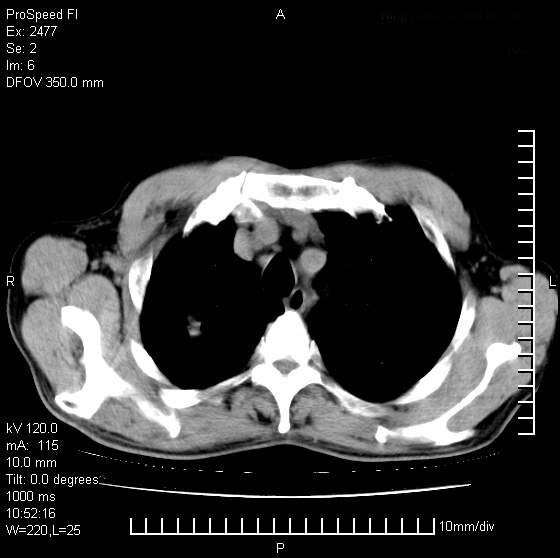

以下是引用天南地北在2007-10-9 14:29:00的发言:[br]1:右上肺结核[br]2:右肺下叶肿块:不支持肺癌,首先考虑炎性病变-肺脓疡可能性大[br]理由:1:临床病史支持,肺脓肿症状不明显应该是不规则服药造成。[br] 2:肿块边缘模糊,周围可见炎性渗出,长毛刺,内见支气管征,不过有点不规则。[br] 我感觉下肺癌这个诊断有点偏左,建议积极抗炎治疗后复查

以下是引用卜一在2007-10-9 15:55:00的发言:[br][br] [br] 1:右上肺结核[br]2:右肺下叶肿块:不支持肺癌,首先考虑炎性病变-肺脓疡可能性大[br]理由:1:临床病史支持,肺脓肿症状不明显应该是不规则服药造成。[br] 2:肿块边缘模糊,周围可见炎性渗出,长毛刺,内见空气支气管征,不过有点不规则。[br] 我感觉下肺癌这个诊断有点偏左,建议积极抗炎治疗后复查![br]支持! [br] [br] [br]

以下是引用wxy7406在2007-10-9 21:02:00的发言:[br]结合临床病史首先考虑感染性病变,但周围型肺癌不能除外,1.患者年龄偏大2.临床有咯血3.(也觉得是最重要的一点)病灶内有偏心性空洞。

以下是引用王仕学在2007-10-9 13:48:00的发言:[br]右下肺周围性肺癌可能性大,最好活检吧

以下是引用hhcckk在2007-10-9 15:18:00的发言:[br]右上肺病灶考虑结核,病灶多种形态并存(纤维化、增殖性病灶并存)[br]右下肺病灶比较难说,个人意见更趋向于“天南地北”的诊断----肺脓肿[br]1、病人有明显的寒战,高热,肿瘤病人很少出现[br]2、病灶周围的肺纹理走向柔和,没有肿瘤病灶常见的集束征[br]3、病灶边缘的毛刺较长,恶性肿瘤多为短毛刺[br]痰中血丝和病人的年龄是两个不利于良性肿块的因素,建议早点活检

以下是引用ydx_74在2007-10-9 15:53:00的发言:[br]右上肺结核,右下中心性肺癌可能大,肺门淋巴结肿大。